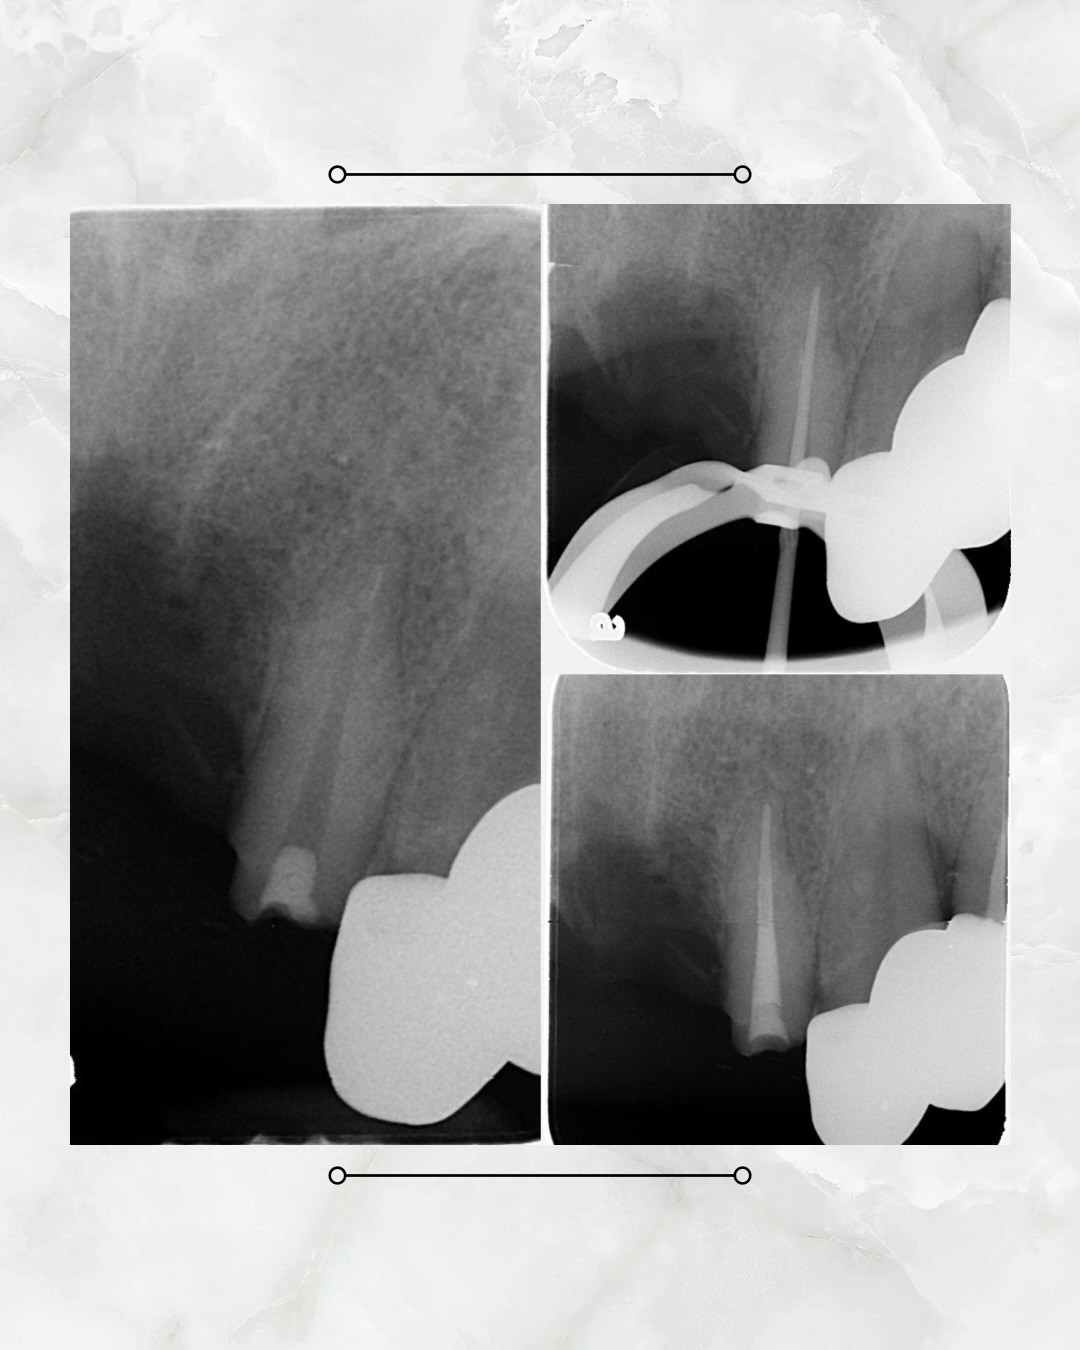

今日很開心可以分享徐子翔副院長的案例,此為較單純的根管治療,通常前牙神經管為1~2根(顎側那一根容易被忽略),此案例展現出徐副院長的特質,仔細檢查後發現只有一個根管,在橡皮帳隔離下清潔根管並封填。治療品質高的徐副院長,可以從根尖端處有一個白影得到印證,此代表者紮實的封填。就小編觀察👀,徐副院長的約診已到月底。